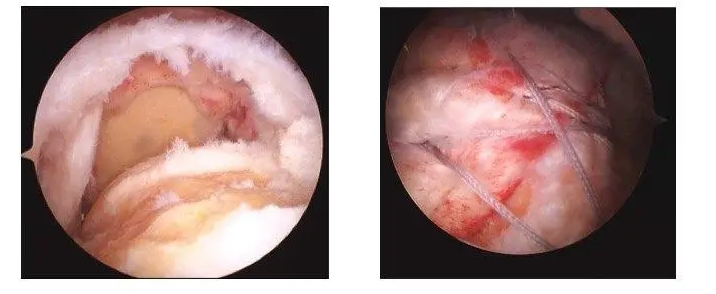

肩關節鏡下肩袖修補術

肩袖(xiù)損傷是臨床上常見的疾病,是指肩關節周圍組織,即岡上肌、岡下肌、小圓肌以及肩胛肌損傷(shāng),臨床主要以疼痛為主,特(tè)別是側臥時,疼痛感嚴重加劇,可引起患者(zhě)功能障礙,影響患者生(shēng)活質量。肩袖損傷疾病主要好發於中老年群體(tǐ)或者是長期從(cóng)事體力勞動者,出現此病的原因是由於肩關節組織(zhī)發生結構磨損,引起此病最主要的因素的是(shì)肩關節撞擊綜(zōng)合征,且岡上(shàng)肌損傷是此病(bìng)常見的表現。肩袖損傷具較(jiào)高的發病(bìng)率,且誤診率偏高,臨床表現夜間疼痛、伴隨肩部乏力、肌力減弱等,且患者運(yùn)動時同樣會伴隨強烈劇痛感。隨著微創技術的發展以及進步,選擇肩關節鏡手術治療此病效果良好(hǎo),具有創(chuàng)傷小、疼痛(tòng)感較低、術中(zhōng)出血量少(shǎo)、術後並發症少、肩關節恢複(fù)速度快等優勢。武(wǔ)寧縣人(rén)民醫院骨科已順利開展關節(jiē)鏡下肩袖修(xiū)補術(shù),且取得較好效果,患者住院周期(qī)為5-7天,創(chuàng)傷小、疼痛感較(jiào)低、恢複(fù)快。

案例:患者吳某,女,62歲,因右肩部(bù)疼痛、活(huó)動受限3個月(yuè)入(rù)院治療。MRI示:右肩(jiān)袖損傷,岡上肌肌(jī)腱斷(duàn)裂,右肩關節退行性改變。入院後完善相關(guān)輔助檢查,在全麻下(xià)+臂叢(cóng)麻醉下行右肩關節鏡下肩袖(xiù)修補術,患(huàn)者術後肩部疼痛明顯緩解(jiě),手術切口小、恢複快,指導患者功能鍛煉,術後第三天康複出院,患(huàn)者對治療效果很滿(mǎn)意。

鏡下圖片